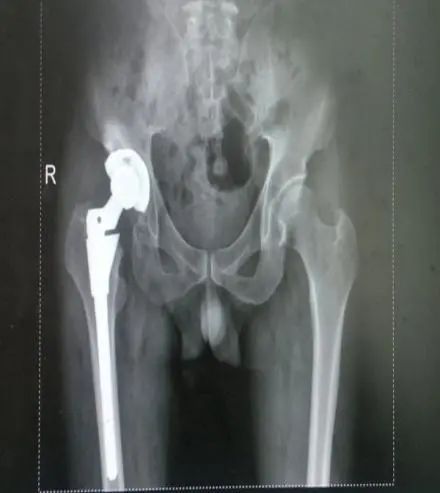

駝背、變矮、腰腿痛

您是否經(jīng)歷過骨折的痛楚?

手術(shù)、住院、難以動彈